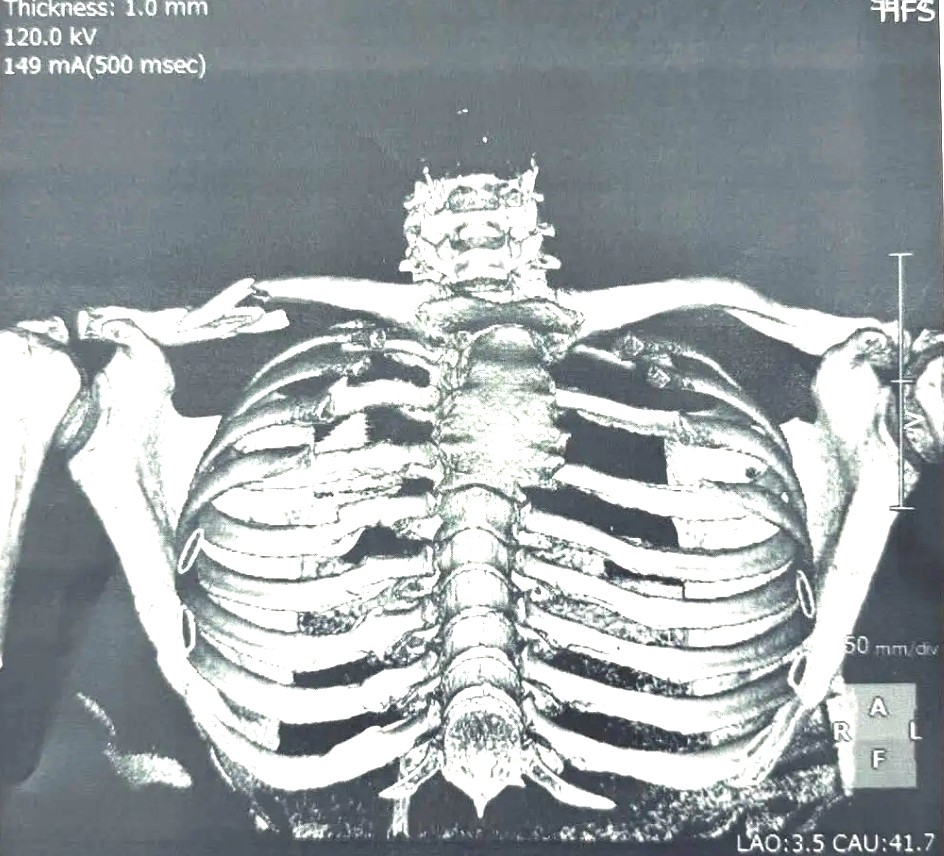

Le scénario est brutal : Martin, trop optimiste sur les freins dès le premier tour, perd le contrôle de sa moto et percute Marco Bezzecchi, provoquant une chute spectaculaire. Verdict : fracture ouverte de la clavicule droite, nouvelle opération à subir, et un coup dur pour un pilote déjà sur la corde raide physiquement.

Il a publié la radio de sa clavicule brisée, deux photos de lui après les premiers examens, ainsi qu’un message tendre adressé à sa compagne et à son père. Mais derrière la façade combative, l’inquiétude grandit. Martinator semble rattrapé par une réalité : celle d’un corps qui encaisse coup sur coup.

Ce nouvel accident soulève une question qui fâche : Martin est-il en train de compromettre sa carrière ? Les blessures s’accumulent : poignet, pied, main… et désormais clavicule ouverte. Chaque absence fragilise sa position face à un paddock toujours plus compétitif.